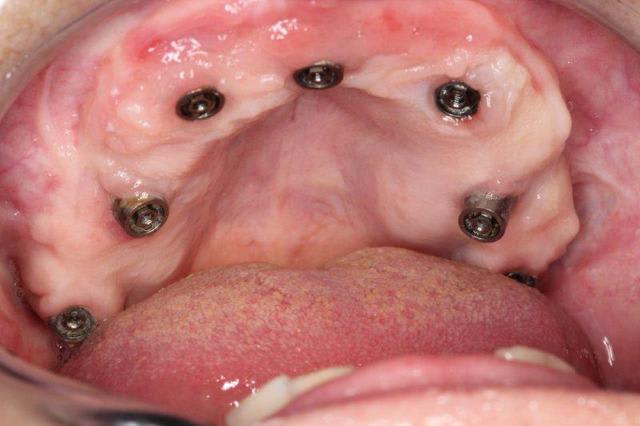

Je vais te filer qques photos d une patiente opérée voici 3 ans avec du nano et des plaques rien que l aspect de la muqueuse te montrera que tout ça est sain et ossifié

Merci, je me souviens bien de ce cas déjà présenté.

Le volume est en effet bien plus grand après, mais je me permet d'avoir quelques doutes sur l'intégration des plaques au niveau osseux...reste à avoir des études et des statistiques sur quelques centaines de cas, voir plus ;-)

Par contre je peux te dire que les 4 plaques et même le monodisk sont sonores et parfaitement indolores donc a priori intégrés béton